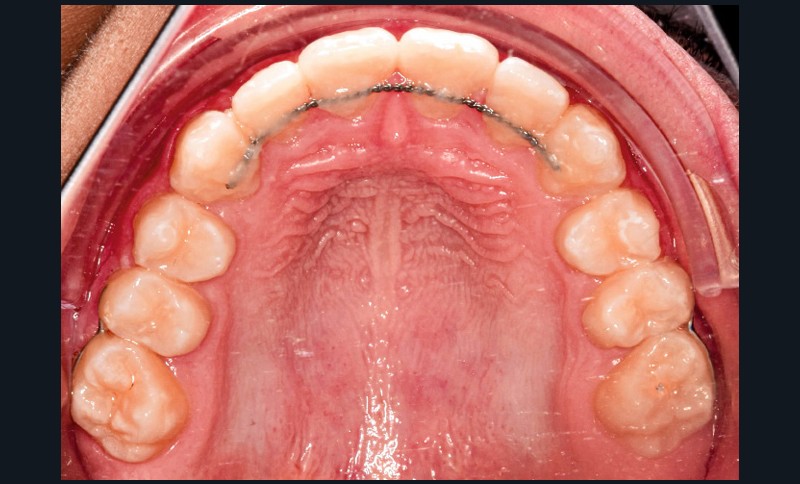

En complément des fils de contention 3-3 bimaxillaires, des contentions (fils collés acier 0.16 x0.22) ont été réalisées entre 15-17, 25-27, 35-37 et 45-47. L’objectif était d’éviter une réouverture des espaces post mésialisation.

Une sur-correction de la rotation de 17 aurait été souhaitable pour optimiser l’alignement et les rapports occlusaux (fig. 2a-d).